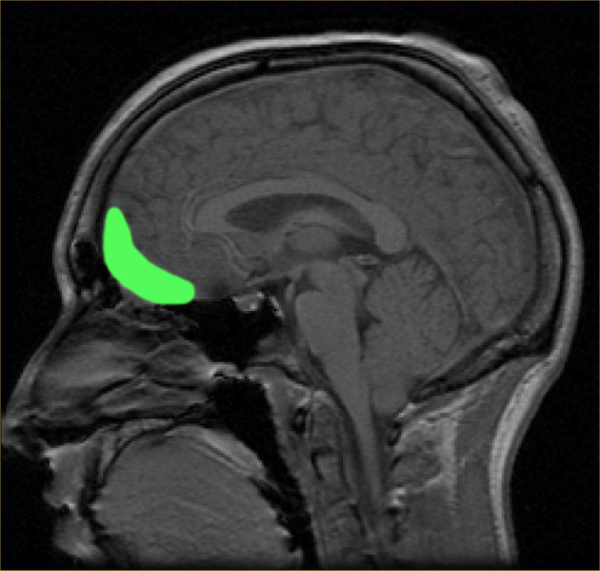

眶额皮层为图中绿色区域。图片来源:wikipedia

根据之前观察的结果,Reinhart教授实验室的博士生Shrey Grover和团队中的其他人推测,操纵眶额皮层(orbitofrontal cortex, OFC)——位于大脑前部奖赏网络中的一个关键区域——的β-γ节律可能会扰乱个体反复选择追求奖赏的能力。研究人员认为,通过这种方式进行干预或许能减少个体与不良习惯相关的强迫行为。